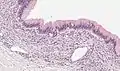

| Micrograph showing a mucinous cystadenoma of the ovary. H&E stain. | |

Microscopy